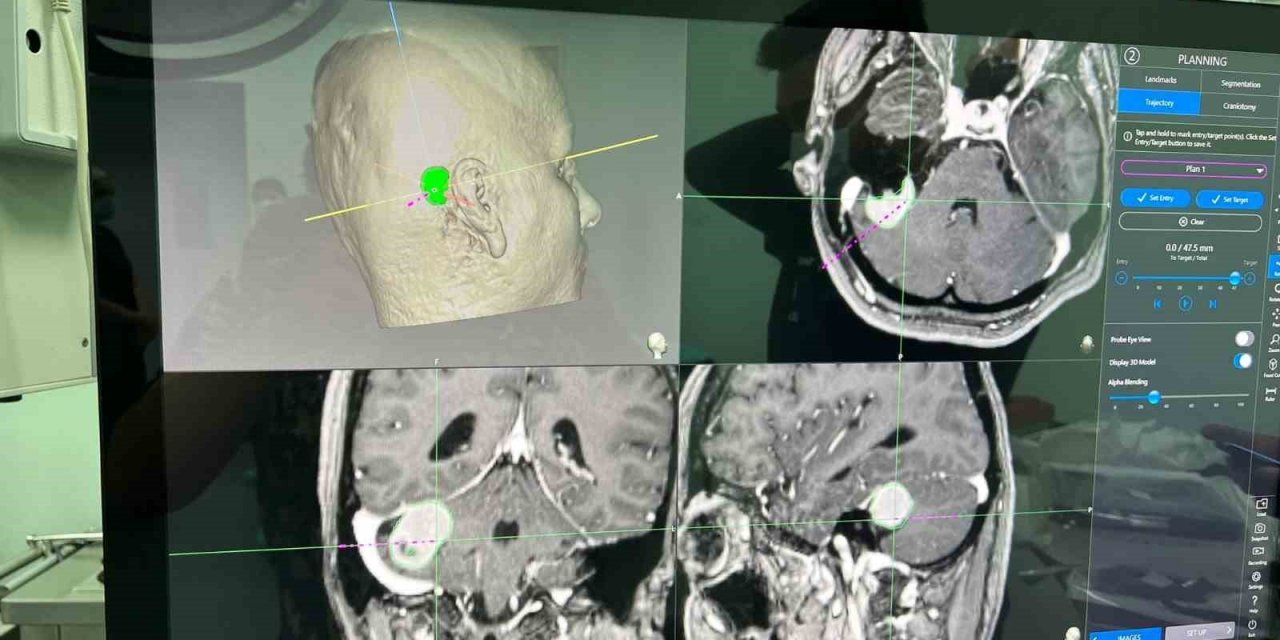

Niğde’de ilk köşe tümörü ameliyatı başarıyla gerçekleştirildi